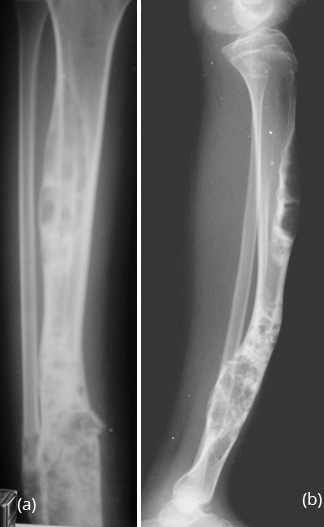

Generally occurs in children less than 10 years. Spontaneous regression is known. Any surgical correction leads to recurrence. Osteofibrous Dysplasia (OD) OD is another entity commonly involving the tibial shaft. Radiologically, an elongated lytic lesion with areas of sclerosis and anterior bowing of the tibia are classical features (Figure 2).

Figure 2a,b: Osteofibrous dysplasia of the tibia. Note the lytic and sclerotic changes scattered. Anterior bowing of the tibia is a characteristic finding.